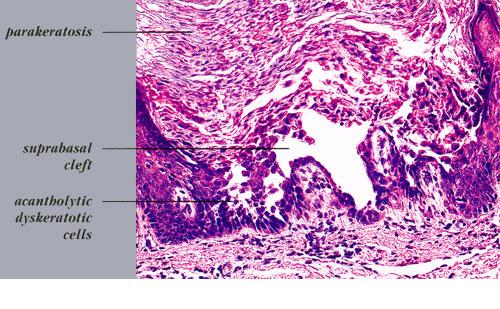

The characteristic changes in Darier’s disease include the following: (a) a peculiar form of dyskeratosis resulting in the formation of corps ronds and grains; (b) suprabasal acantholysis leading to the formation of suprabasal clefts or lacunae; and (c) irregular upward proliferation into the lacunae of papillae lined with a single layer of basal cells, so-called villi (Fig. 6-27). There are also papillomatosis, acanthosis, and hyperkeratosis. The dermis shows a chronic inflammatory infiltrate. In some cases, there is downward proliferation of epidermal cells into the dermis.

The corps ronds occur in the upper stratum malpighii, particularly in the granular and horny layers; grains are found in the horny layer and as acantholytic cells within the lacunae. Corps ronds possess a central homogeneous, basophilic,

pyknotic nucleus that is surrounded by a clear halo. By virtue of size and the conspicuous halo, corps ronds stand out clearly . Peripheral to the halo lies basophilic dyskeratotic material as a shell . The nonstaining halo in some instances is partially replaced by homogeneous, eosinophilic dyskeratotic material . Compared with the corps ronds, the grains are much less conspicuous. They resemble parakeratotic cells but are somewhat larger. The nuclei of grains are elongated and often grain shaped and are surrounded by homogeneous dyskeratotic material that usually stains basophilic but may stain eosinophilic. The lacunae represent small, slitlike intraepidermal vesicles most commonly located directly above the basal layer. They contain acantholytic cells and show premature partial keratinization. Because of shrinkage, some of them are elongated, and these then appear identical with the grains in the horny layer. The villi projecting into the lacunae may be quite tortuous, so on histologic examination, some of them appear in cross section as rounded dermal structures lined by a solitary row of basal cells .